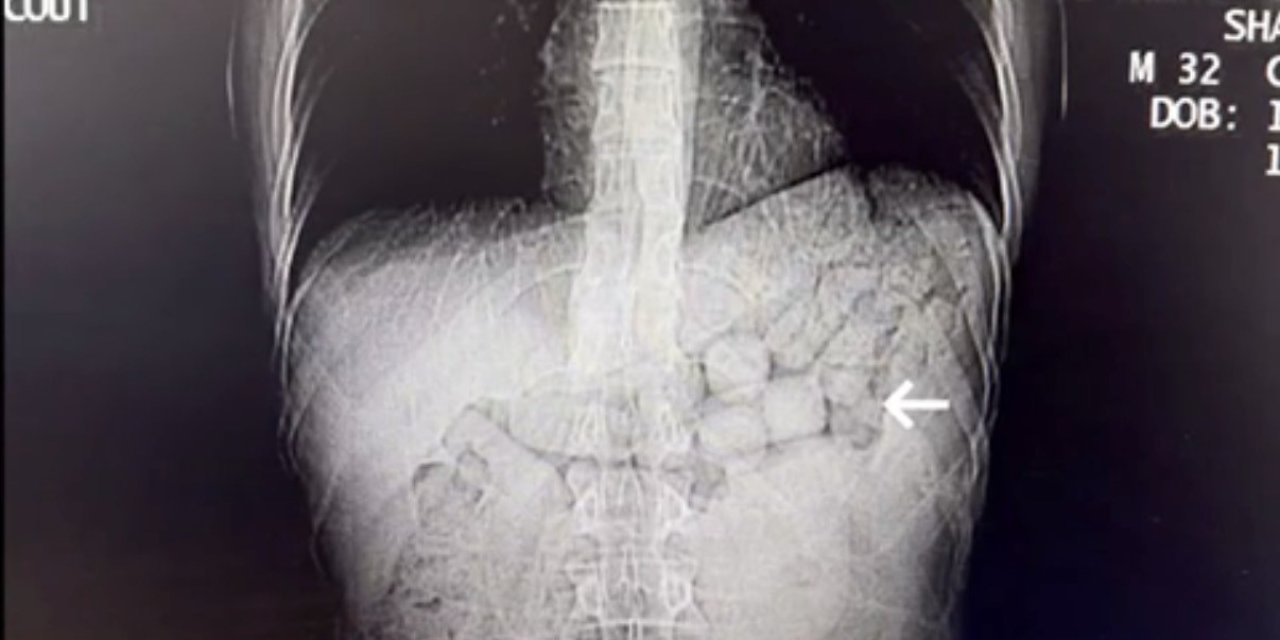

Ölmez, 24 Nisan 2024’te ateş şikâyetiyle hastaneye götürülen kızı Aleyna Ölmez’in yaklaşık bir hafta boyunca tedavi gördüğünü, bu süreçte sağlık durumunun ağırlaştığını ve sevk taleplerinin kabul edilmediğini ileri sürdü. Ailenin kendi imkânlarıyla Van Eğitim ve Araştırma Hastanesi’ne götürdüğü Aleyna Ölmez’e burada Stevens-Johnson Sendromu tanısı konulduğu belirtildi.

Anne Ölmez, Aleyna’nın uzun süre yoğun bakımda kaldığını, iki gözünü kaybettiğini ve kalıcı sağlık sorunları oluştuğunu aktardı. Daha sonra İstanbul Başakşehir Çam ve Sakura Şehir Hastanesi ile İstanbul Özel Çağdaş Laboratuvarı’nda yapılan tahlillerde bazı ilaçlara karşı yüksek antikor değerleri tespit edildiğini öne sürdü ve bu raporların dosyaya eklenmesini talep etti.